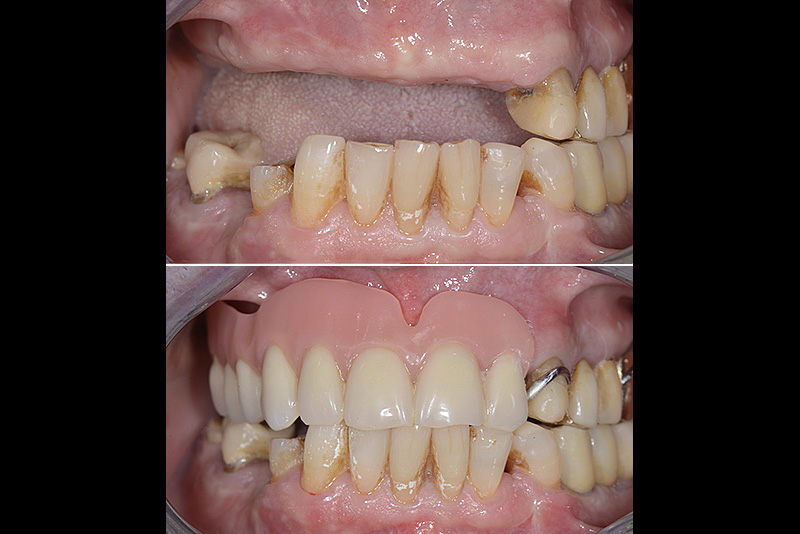

PREMESSA: in seguito all’estrazione dell’incisivo laterale superiore di destra, resasi necessaria per cause batteriche, si decide di affrontare il caso con il posizionamento di un impianto in sostituzione dell’elemento mancante dopo guarigione del sito infetto. Con tecniche rigenerative sia dei tessuti ossei mancanti a causa dell’infezione pregressa, sia dei tessuti gengivali che appaiono inizialmente troppo spostati in alto, si ripristina una corretta morfologia delle parabole (contorni) gengivali e delle papille interdentali (triangoli di gengiva tra due denti vicini).

Vengono utilizzati 2 tipi di provvisori: il primo, cementato ai denti vicini, viene utilizzato dal momento dell’estrazione del dente fino ad impianto osteointegrato (circa 6 mesi); il secondo, avvitato direttamente all’impianto, ha una funzione di prova estetica ma soprattutto di guida per la maturazione dei tessuti gengivali peri-implantari portandoli verso la maturazione completa prima di posizionare la corona finale in disilicato di litio.